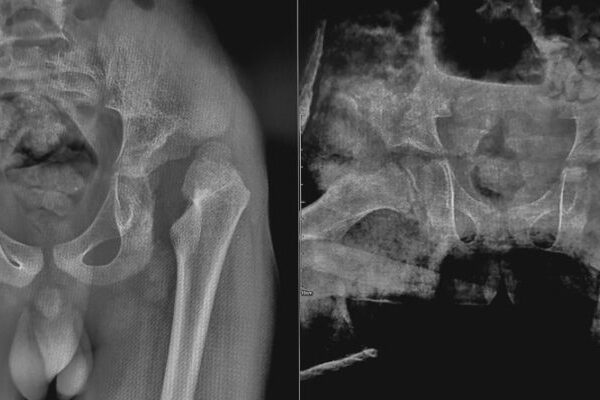

HSG (Rahim) Filmi Önce Dikkat Edilmesi Gereken 5 Şey Histerosalpingografi, bilinen adıyla HSG filmi ya da “rahim filmi”, rahim iç boşluğunu ve tüplerin açıklığını değerlendirmek için uygulanan kısa ama titiz bir görüntüleme tetkikidir. Kısırlık araştırmasının temel taşlarından biri olan bu işlem, doğru gün seçimi, enfeksiyon riskinin azaltılması ve ağrı yönetimi gibi ayrıntılara dikkat edildiğinde çok […]